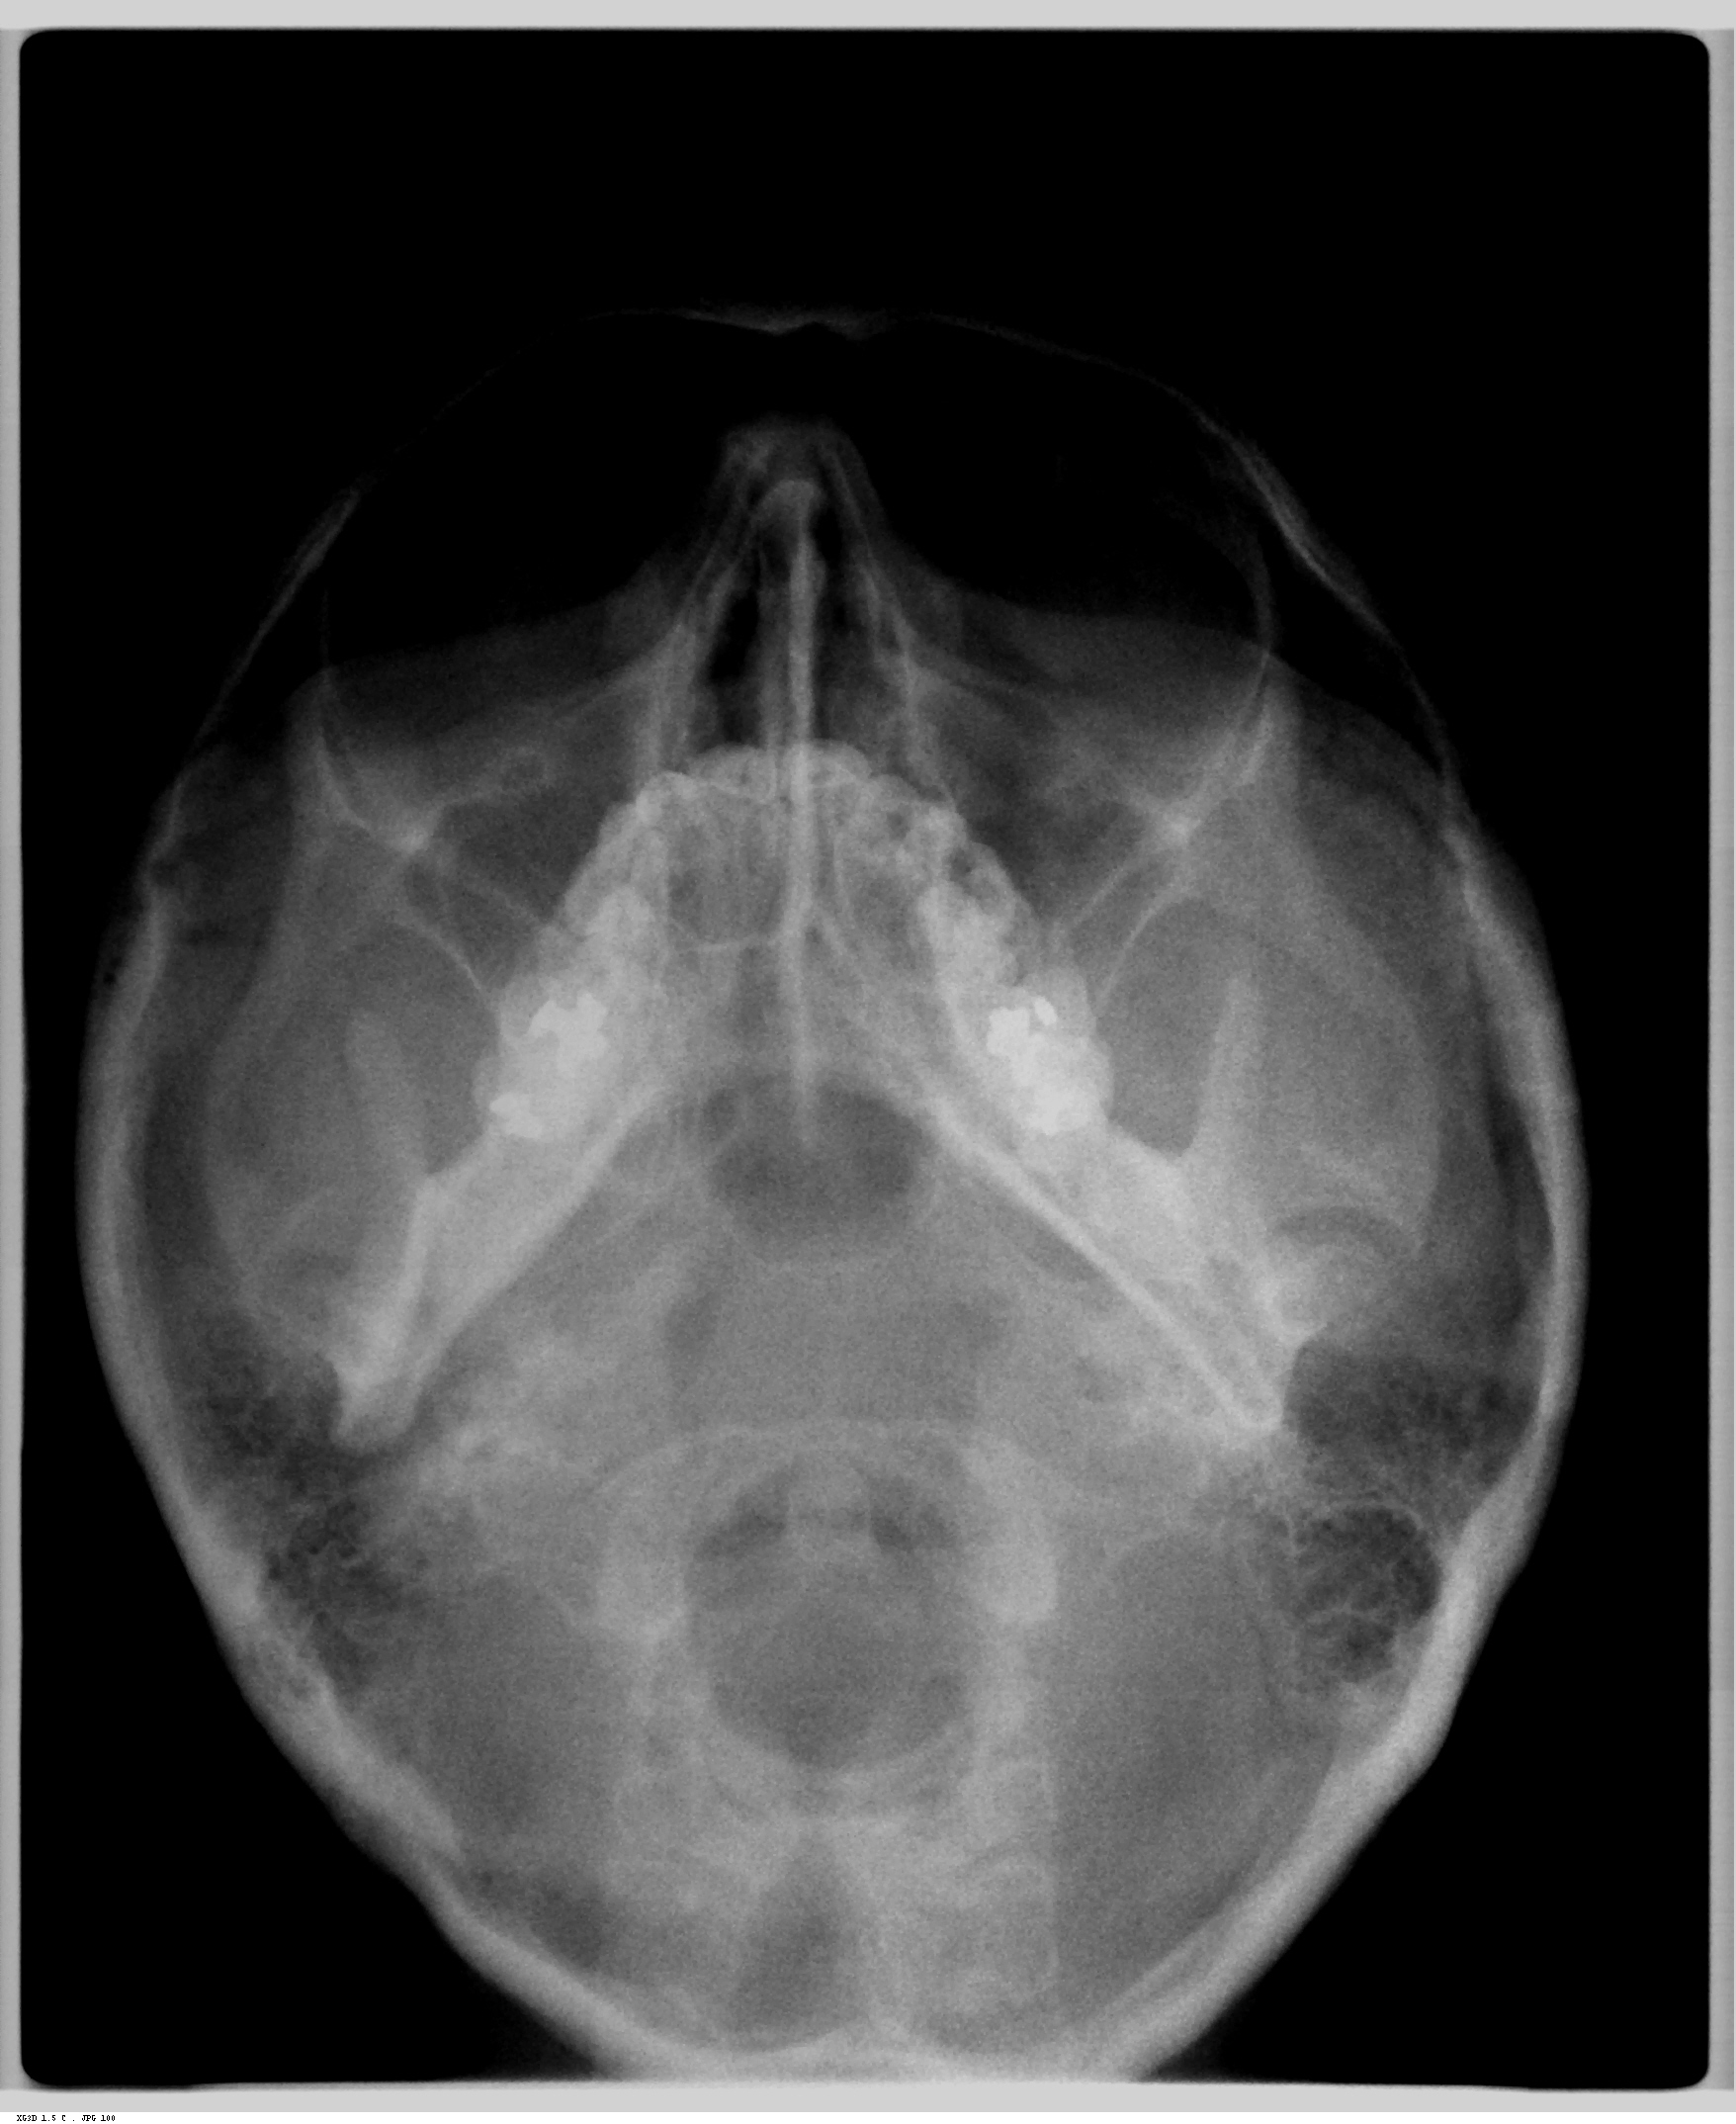

.Axial (Projeção de Hirtz)

Indicações

- para pesquisa e localização das fraturas do arco zigomático.

- para pesquisa da integridade da parede posterior do seio maxilar.

- para exame da mandíbula (processo coronoide e côndilo.